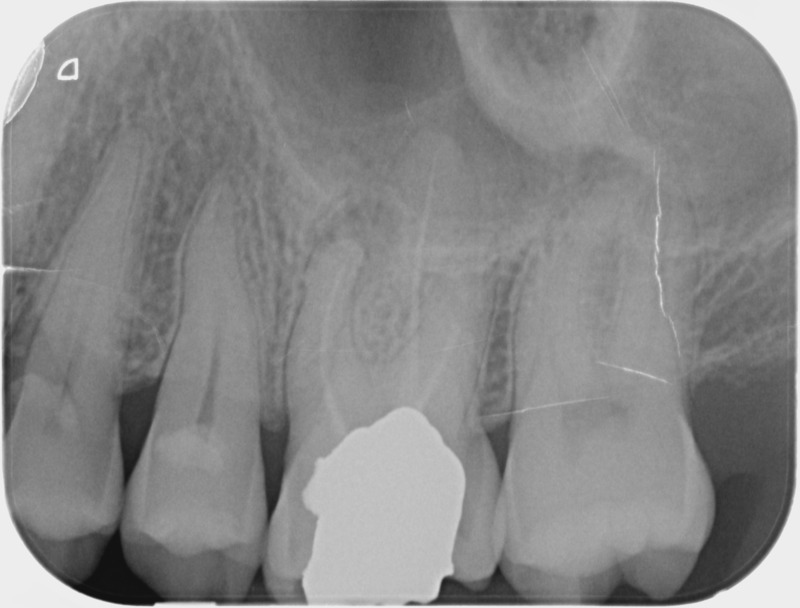

• Apexification : Chez le jeune enfant, une dent immature victime d’un traumatisme ou d’une carie volumineuse peut poser problème. Si la pulpe agressée se nécrose, alors la racine ne s’édifie plus et une lésion inflammatoire se développe au niveau osseux. L’apexification, par apposition d’un matériau biocompatible dans la racine, cherche à induire la formation d’une barrière artificielle à l’extrémité de celle-ci, et permettre la cicatrisation de la lésion dans le but de maintenir la dent en bouche à long terme.

Avant

Après